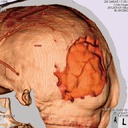

| Features | 1.Radiology absorption and HU number approximate to human body 2. Main joints have close-to human articulation 3. Phantom can be disassembled into 10 individual parts |

| Case / Pathology | Refer to PDF( Anatomy and Pathologies) |

| Materials | Soft tissue: urethane based resin (density: 1.06) Synthetic bone: epoxy resin (density: 1.31) Skull:epoxy resin (density: 1.11) *Phantom has no metal parts or liquid structure |